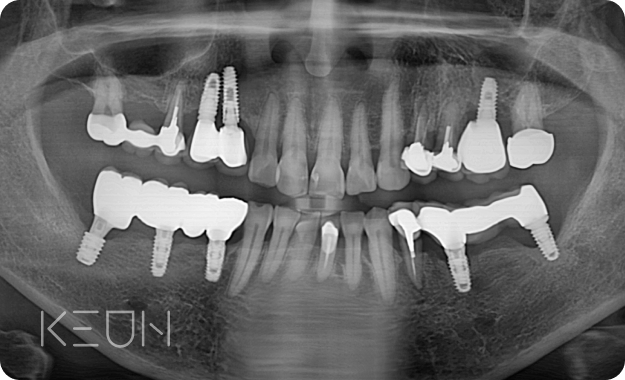

임플란트 재치료.

임플란트는 대중화되어 제 3의 치아라는 명칭을 얻고 있지만,

보철물의 수명, 시술 중 발생하는 문제, 사후관리 미흡 등으로 재치료를 받는 경우가 많습니다.

- Before

- After